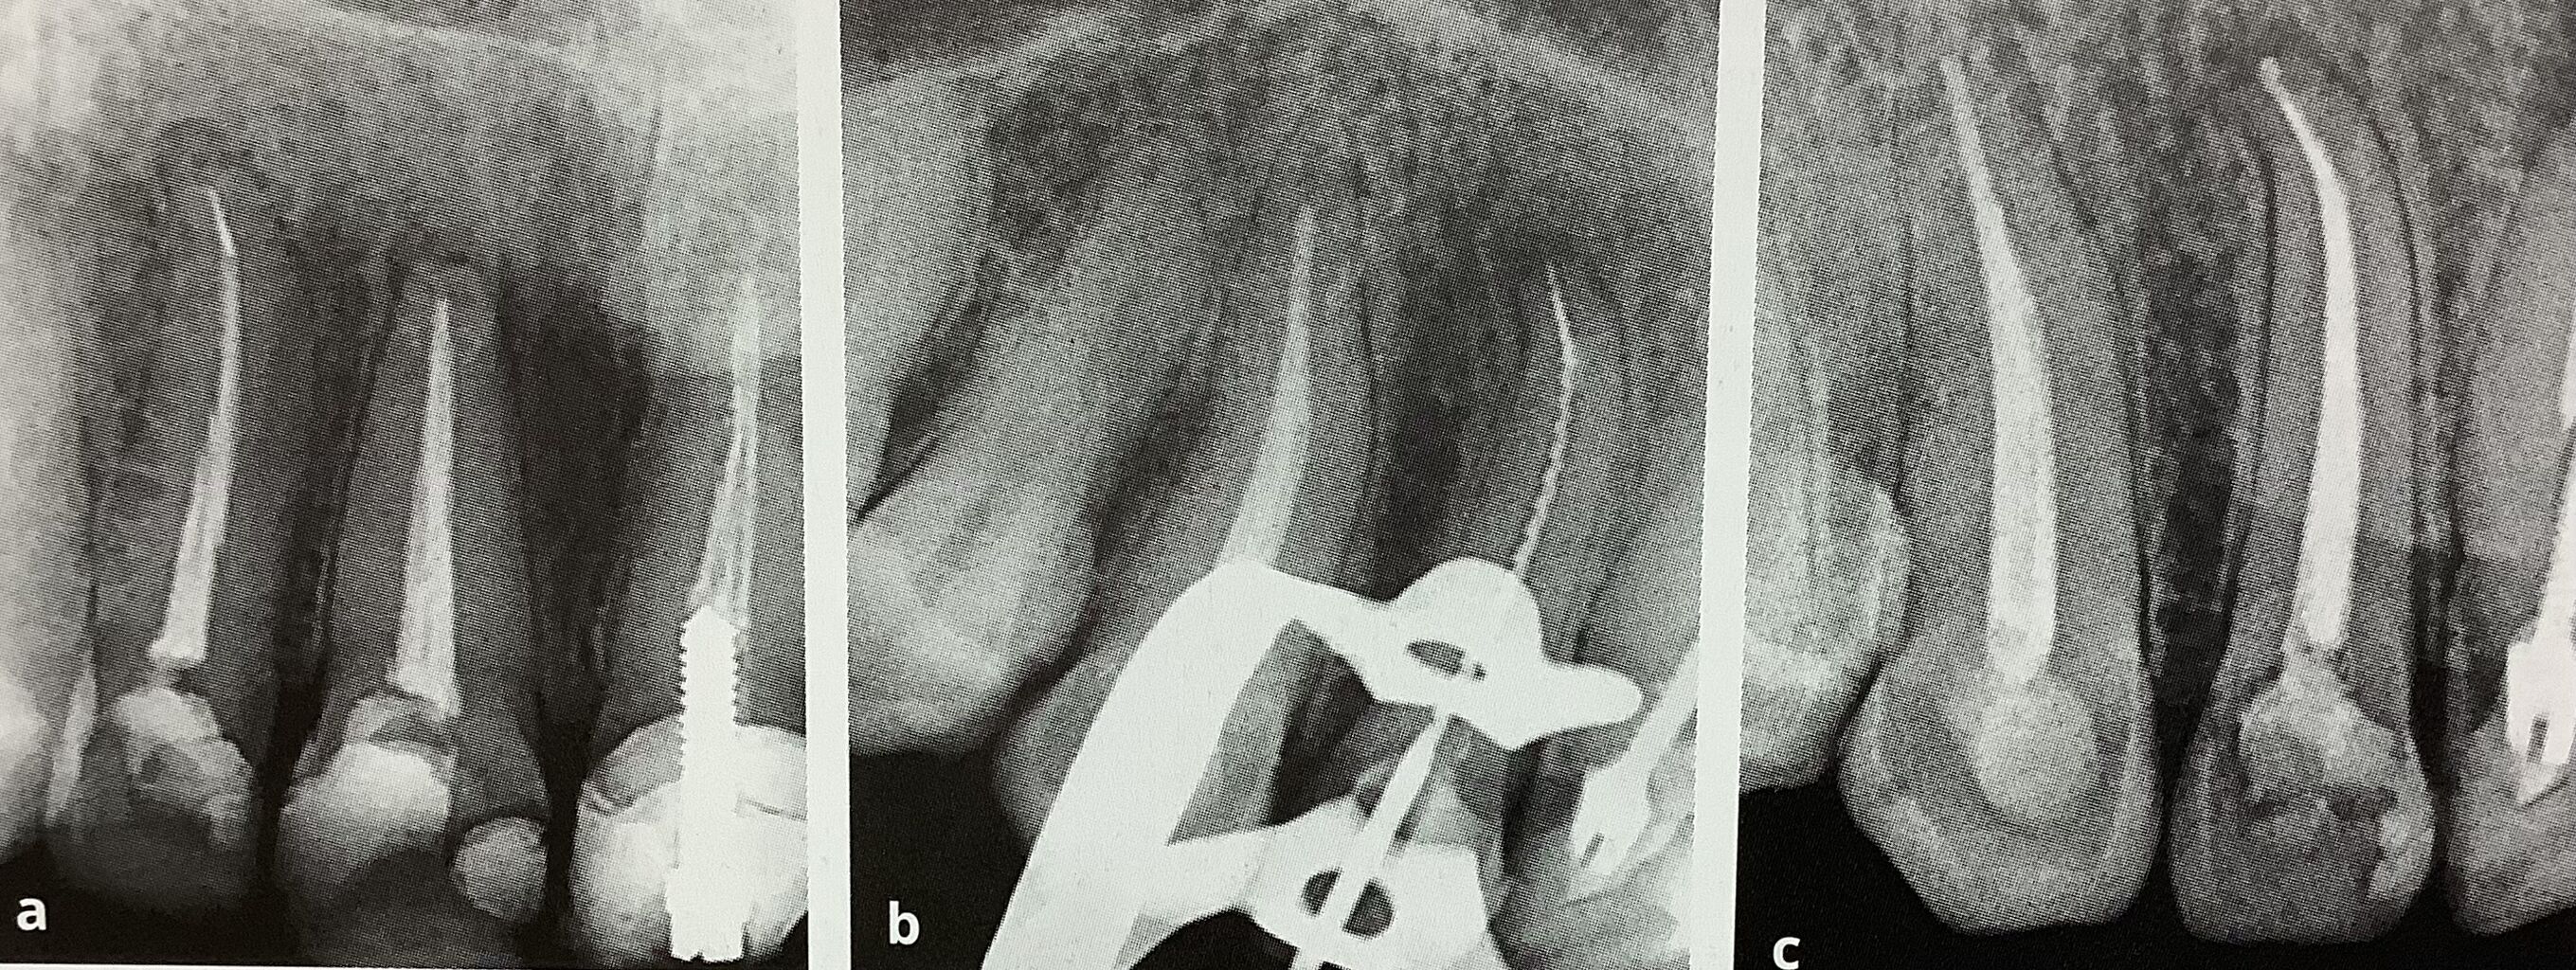

真ん中の前歯、1番はぶつけて神経に治療して、治んなくて外科手術を受けたそうです。

短いですね。

で隣の2番も神経の反応が無かったので、神経を取ったそうですが、

真っ直ぐの方へ誤って削ってしまい、外科治療をして欲しいと紹介されました。

普通に再根管治療をして、16年後に何ら問題ないのが右下です。